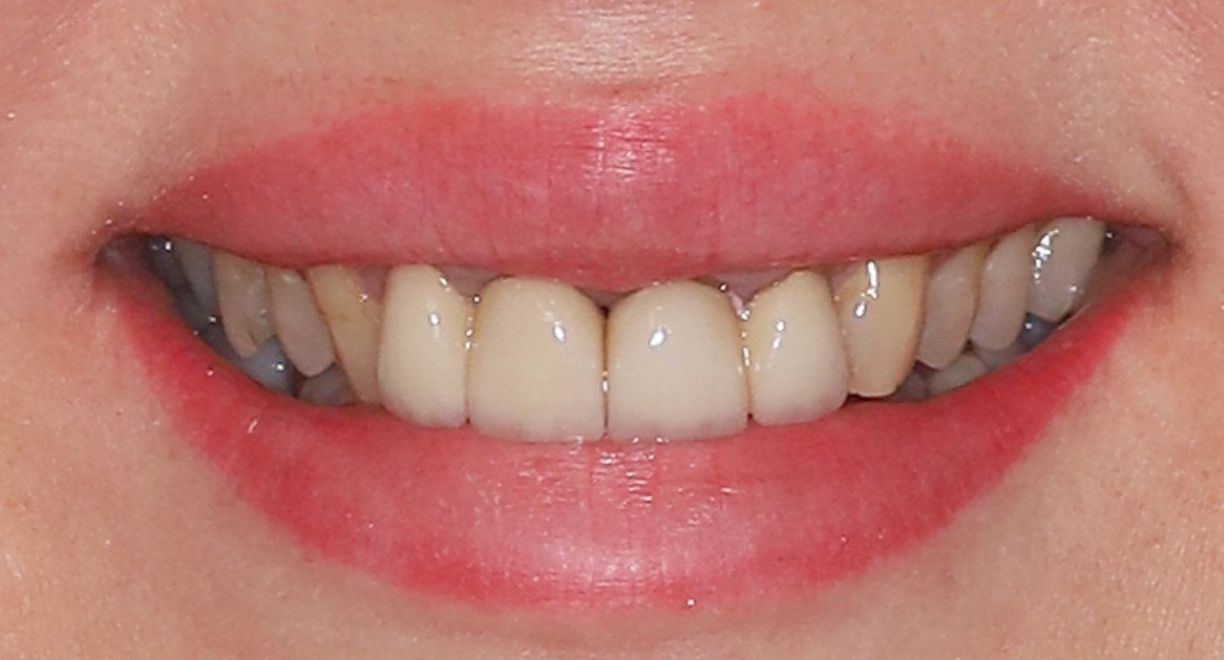

• Single-Tooth Dental Implant Placement + Dental Veneers for Full Smile Aesthetics

The patient was missing one tooth, and based on a detailed clinical evaluation, an individualized treatment plan was created. A titanium dental implant was placed into the jawbone, functioning as an artificial tooth root and providing a stable foundation for long-term restoration. After complete osseointegration, a custom-made zirconia crown was fabricated. It accurately replicates the natural tooth’s color, shape, and anatomy, restoring both chewing function and aesthetics. The neighbouring teeth are not affected during the treatment and remain intact. To ensure full smile aesthetics and a harmonious final result, dental veneers were also placed for the patient.